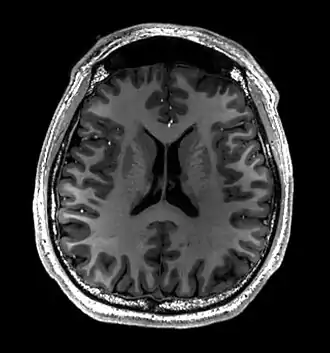

Normal axial T2-weighted MR image of the brain

- T1-weighted (T1W) images: Cerebrospinal fluid is dark. T1-weighted images are useful for visualizing normal anatomy.